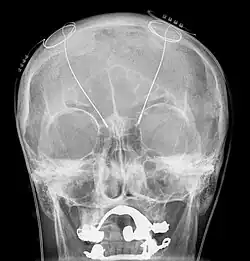

The leads are two coiled wires insulated in polyurethane with four platinum-iridium electrodes that allow delivery of electric charge from the battery pack implanted in the chest wall. The battery is usually situated subcutaneously below the clavicle and rarely in the abdomen. The leads, in turn, are connected to the battery by an insulated extension wire which travels from the chest wall superiorly along the back of the neck below the skin, behind the ear, and finally enters the skull through a surgically made burr hole to terminate in the deep nuclei of the brain.[19] Microelectrodes (usually 1–5) are delivered through the burr holes. A combination of microelectrode recordings, microstimulation, macrostimulation, and neurophysiological mapping at the level of single neurons or local neuronal populations through local field potential analyses are used to increase specificity of placement for the most precise neurophysiologic effect possible.[2]

DBS leads are placed in the brain according to the specific symptoms to be addresses and implantation may take place under local or general anesthesia. A hole about 14 mm in diameter is drilled in the skull and the probe electrode is inserted stereotactically, using either frame-based or frameless stereotaxis.[21] During the awake procedure with local anesthesia, feedback from the individual is used to determine the optimal placement of the permanent electrode. During the asleep procedure, intraoperative MRI is used to image the brain during device placement.[22] The installation of the IPG and extension leads occurs under general anesthesia.[23]

Because the brain can shift slightly during surgery, the electrodes can become displaced or dislodged, though electrode misplacement can be suspected by lack of clinical effect when the leads are turned on and a sudden dramatic increase in electrode impedance. The displacement can be physically located using CT scan, which would then guide a repeat intervention for repositioning. After surgery, swelling of the brain tissue, mild disorientation, and sleepiness are normal. After 2–4 weeks, the sutures are removed and the neurostimulator is activated.[154]